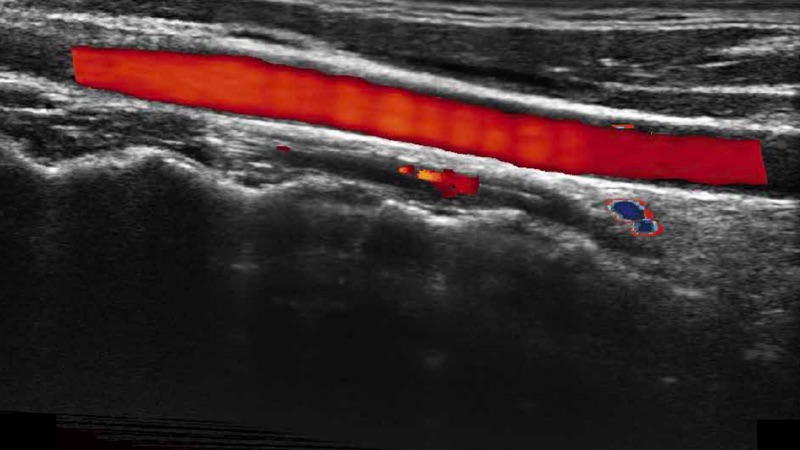

高分辨率血流成像技術提高了對低速血流信號的檢測能力。在提高空間分辨率的同時,也克服了血流外溢現象,為用戶提供更加真實的血流動力學信息。